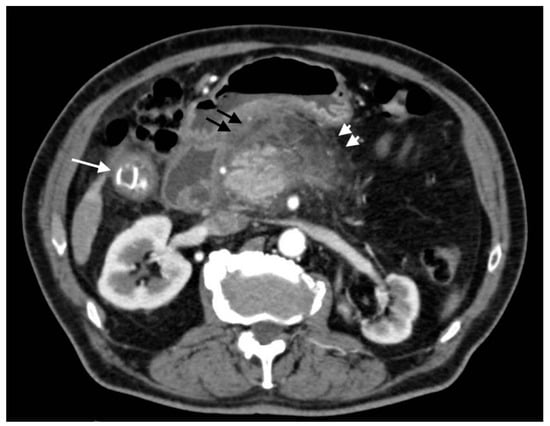

Hepatic artery aneurysms are very rare, accounting for 20% of visceral splanchnic aneurysms (1% of all aneurisms). Pseudoaneurysm represents over 50% of hepatic artery aneurysms, which differ from true aneurysms because they do not involve the entire arterial wall but only a focal wall defect surrounded by fibrotic material, leading to a false layer [28]. Nevertheless, the risk of rupture is significantly higher for pseudoaneurysms [24]. It can be responsible for hemobilia [23]. The literature, and our experience, suggests that acute cholecystitis represents a potential cause of pseudoaneurysms; in fact, as reported in the literature, severe inflammation can cause adjacent arterial wall degeneration, resulting in pseudoaneurysm formation [28,29,30]. For acute cholecystitis, cystic and right hepatic arteries are generally involved [24]. CT shows this lesions as an abnormal vessel dilatation with irregular contour and sometimes surrounded by hematomas. Hepatic artery pseudoaneurysm could be seen as an artery-phase homogenously enhanced intrahepatic mass (Figure 12); however, it may also be detected extrahepatically when it originates from the common or proper hepatic arteries [24]. Diagnostic assessment is fundamental for proper treatment: recently, endovascular treatment (percutaneous embolization or stent grafting) is preferred to surgical repair [31]; however, this type of lesion may resolve spontaneously [32].

Figure 12.

Right hepatic artery pseudoaneurysm: (a) axial image in the arterial phase shows an abnormal dilation of the right hepatic artery (black arrow); wedge-shaped area of parenchymal hypodensity (white arrow) secondary to hypoperfusion; (b) sagittal image better demonstrates continuity of the abnormal dilation (arrow) with a right hepatic artery branch (arrowhead).